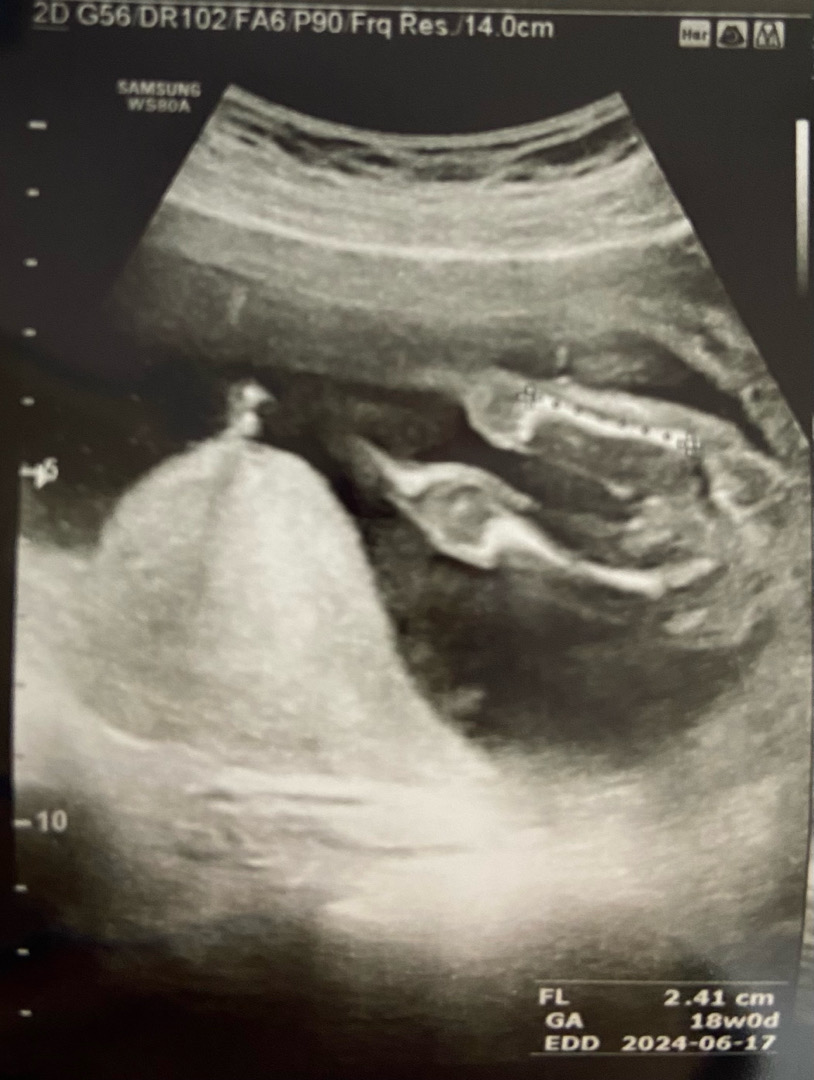

17주 3일 초음파 사진이예요👉👈 여러분 의견이 궁금해요!! 다리사이에 하얗게 보이 두개 알맹이는 탯줄일까요??

딸인데요! 아들이면 가운데 뾰족한게 보여야되는데 안보여요

저는 아들같아요~ 우리딸램 초름파랑 조금 달라서요 밖으로 나온거 뽕알같고, 딸은 줄이 세개가 있어요 가운데에